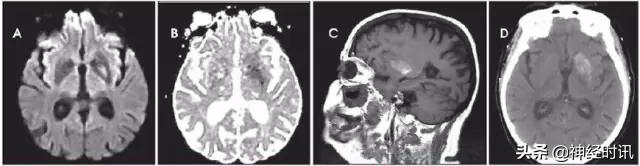

感染性脑炎和脓肿

在临床上,脑炎或脑脓肿可能被误诊为脑卒中。早期脑炎可表现为模糊的T2高信号病变,伴有弥散受限及轻微增强或无增强(图21)。

细菌性脓肿通常表现为界限清楚的强化环,并伴有中央弥散受限和周围水肿。这种表现在晚期亚急性卒中患者中也可见到,但并不普遍。而真菌性脓肿的边缘可能不太清楚,因而更容易与卒中相混淆。化脓性脑脓肿存在弥散受限的原因与水分在化脓性脑脊液内的扩散受到限制有关。脑炎患者的弥散受限则可能与坏死性血管炎或静脉血栓形成所致的细胞毒性水肿相关。

图21 一例70岁老年男性,患有糖尿病、非缺血性心肌病,且左室辅助装置并发了真菌性脓肿。MRI显示其左侧枕叶存在一个不规则的边缘薄层增强病变(D:T1WI增强),伴有弥散受限(B:DWI,C:ADC)、磁化率效应环(E:SWI)和周围的T2高信号改变(A:FLAIR)。